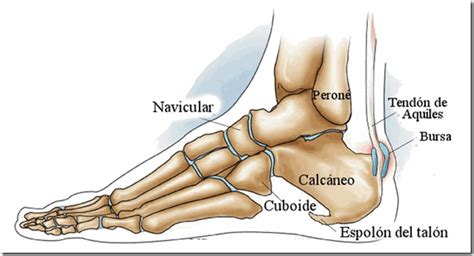

¿Qué es el espolón calcáneo?

¿Qué es el Espolón calcáneo? ¿Por qué aparece y por qué duele?